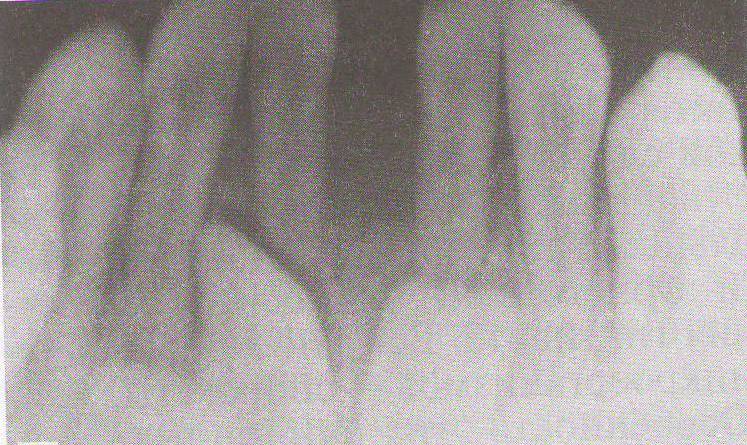

| Рис. 18. Нависающий край пломбы у 46 зуба. Деструкция межзубной перегородки у корня 46 зуба, костный карман. Высота межзубной перегородки у 46 зуба снижена на 1/3 длины корня. Рис. 19. Локализованный пародонтит в области 44,45,46 из-за отсутствия контактных пунктов. Снижение высоты межзубных перегородок на 1/3. Расширение периодонтальной щели 45. Остеопороз. Рис. 20. Снижение межзубной перегородки между 31 и 41 зубами на 2/3 длины корня, остеопороз. Локализованный пародонтит тяжелой степени. Рис. 21. Глубокое резцовое перекрытие. Мелкое преддверие полости рта. Высота межзубных перегородок на уровне эмалево-цементной границы. Деструкция кортикальных пластинок вершин межзубных перегородок. Расширение периодонтальной щели в боковых отделах. Остеопороз межзубных перегородок. |